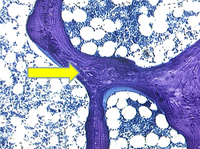

Fotomicrografia de biópsia óssea transilíaca de um paciente com osteomalácia demonstrando osteoide desmineralizado (mostrado em roxo). A largura dos osteoides é aumentada substancialmente

Do acervo de Bridget Sinnott, MD; usado com permissão